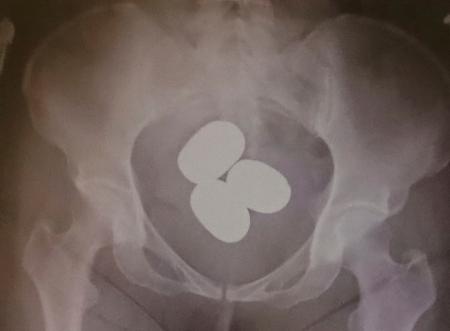

東京税関成田税関支署が公表した、香港からの旅客が体内に粉状の金を隠し密輸しようとした摘発事例(同署提供)

東京税関成田税関支署は24日、粉状の金を避妊具などに入れて体内に隠し、香港から成田空港へ密輸するケースが急増していると明らかにした。今年1~3月に押収しただけで時価総額は約12億円に上る。不安定な国際情勢を背景に金の価格は高騰しており、正規の輸入で納めなければならない消費税を免れ、利ざやを得る目的とみている。

成田税関支署によると、成田空港で粉状の金の摘発は昨年1年間で23件、計約31キロ。今年は3月までに30件、計約45キロで、いずれも香港や中国籍の旅客が、粉状の金を空港到着後などに体内に隠し、持ち込もうとした。中高年の女性が多く、複数の塊に分けて約2・7キロ分を密輸しようとした男性もいたという。